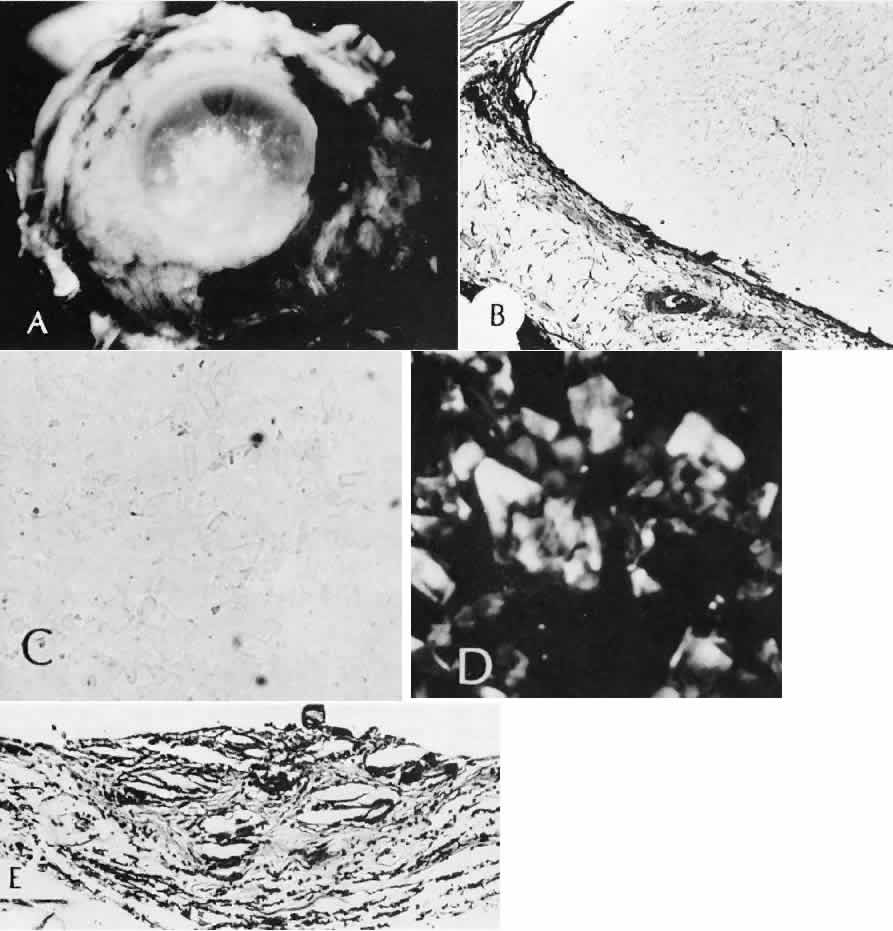

epithelium. Current Eye Research 16(4):349–358, 1997. 50. Perry DD, Reddick RL, Risco JM: Choroidal microvascular repair after argon laser photocoagulation. Ultrastructural

observations. Investigative Ophthalmology & Visual Science 25(9):1019–1026, 1984. 51. Perry DD, Risco JM: Choroidal microvascular repair after argon laser photocoagulation. American Journal of Ophthalmology 93(6):787–793, 1982. 52. Hayashi A et al: Surgically induced degeneration and regeneration of the choriocapillaris

in rabbit. Graefes Archive for Clinical & Experimental Ophthalmology 237(8):668–677, 1999. 53. Pollack A, Korte GE: Restoration of the outer blood-retinal barrier after krypton laser photocoagulation. Ophthalmic Research 25(4):201–209, 1993. 54. Miller H et al: Pathogenesis of laser-induced choroidal subretinal neovascularization. Investigative Ophthalmology & Visual Science 31(5):899–908, 1990. 55. Jacobs B, Gaynes B, Dutsch T: Refractive astigmatism after oblique clear corneal phacoemulsification